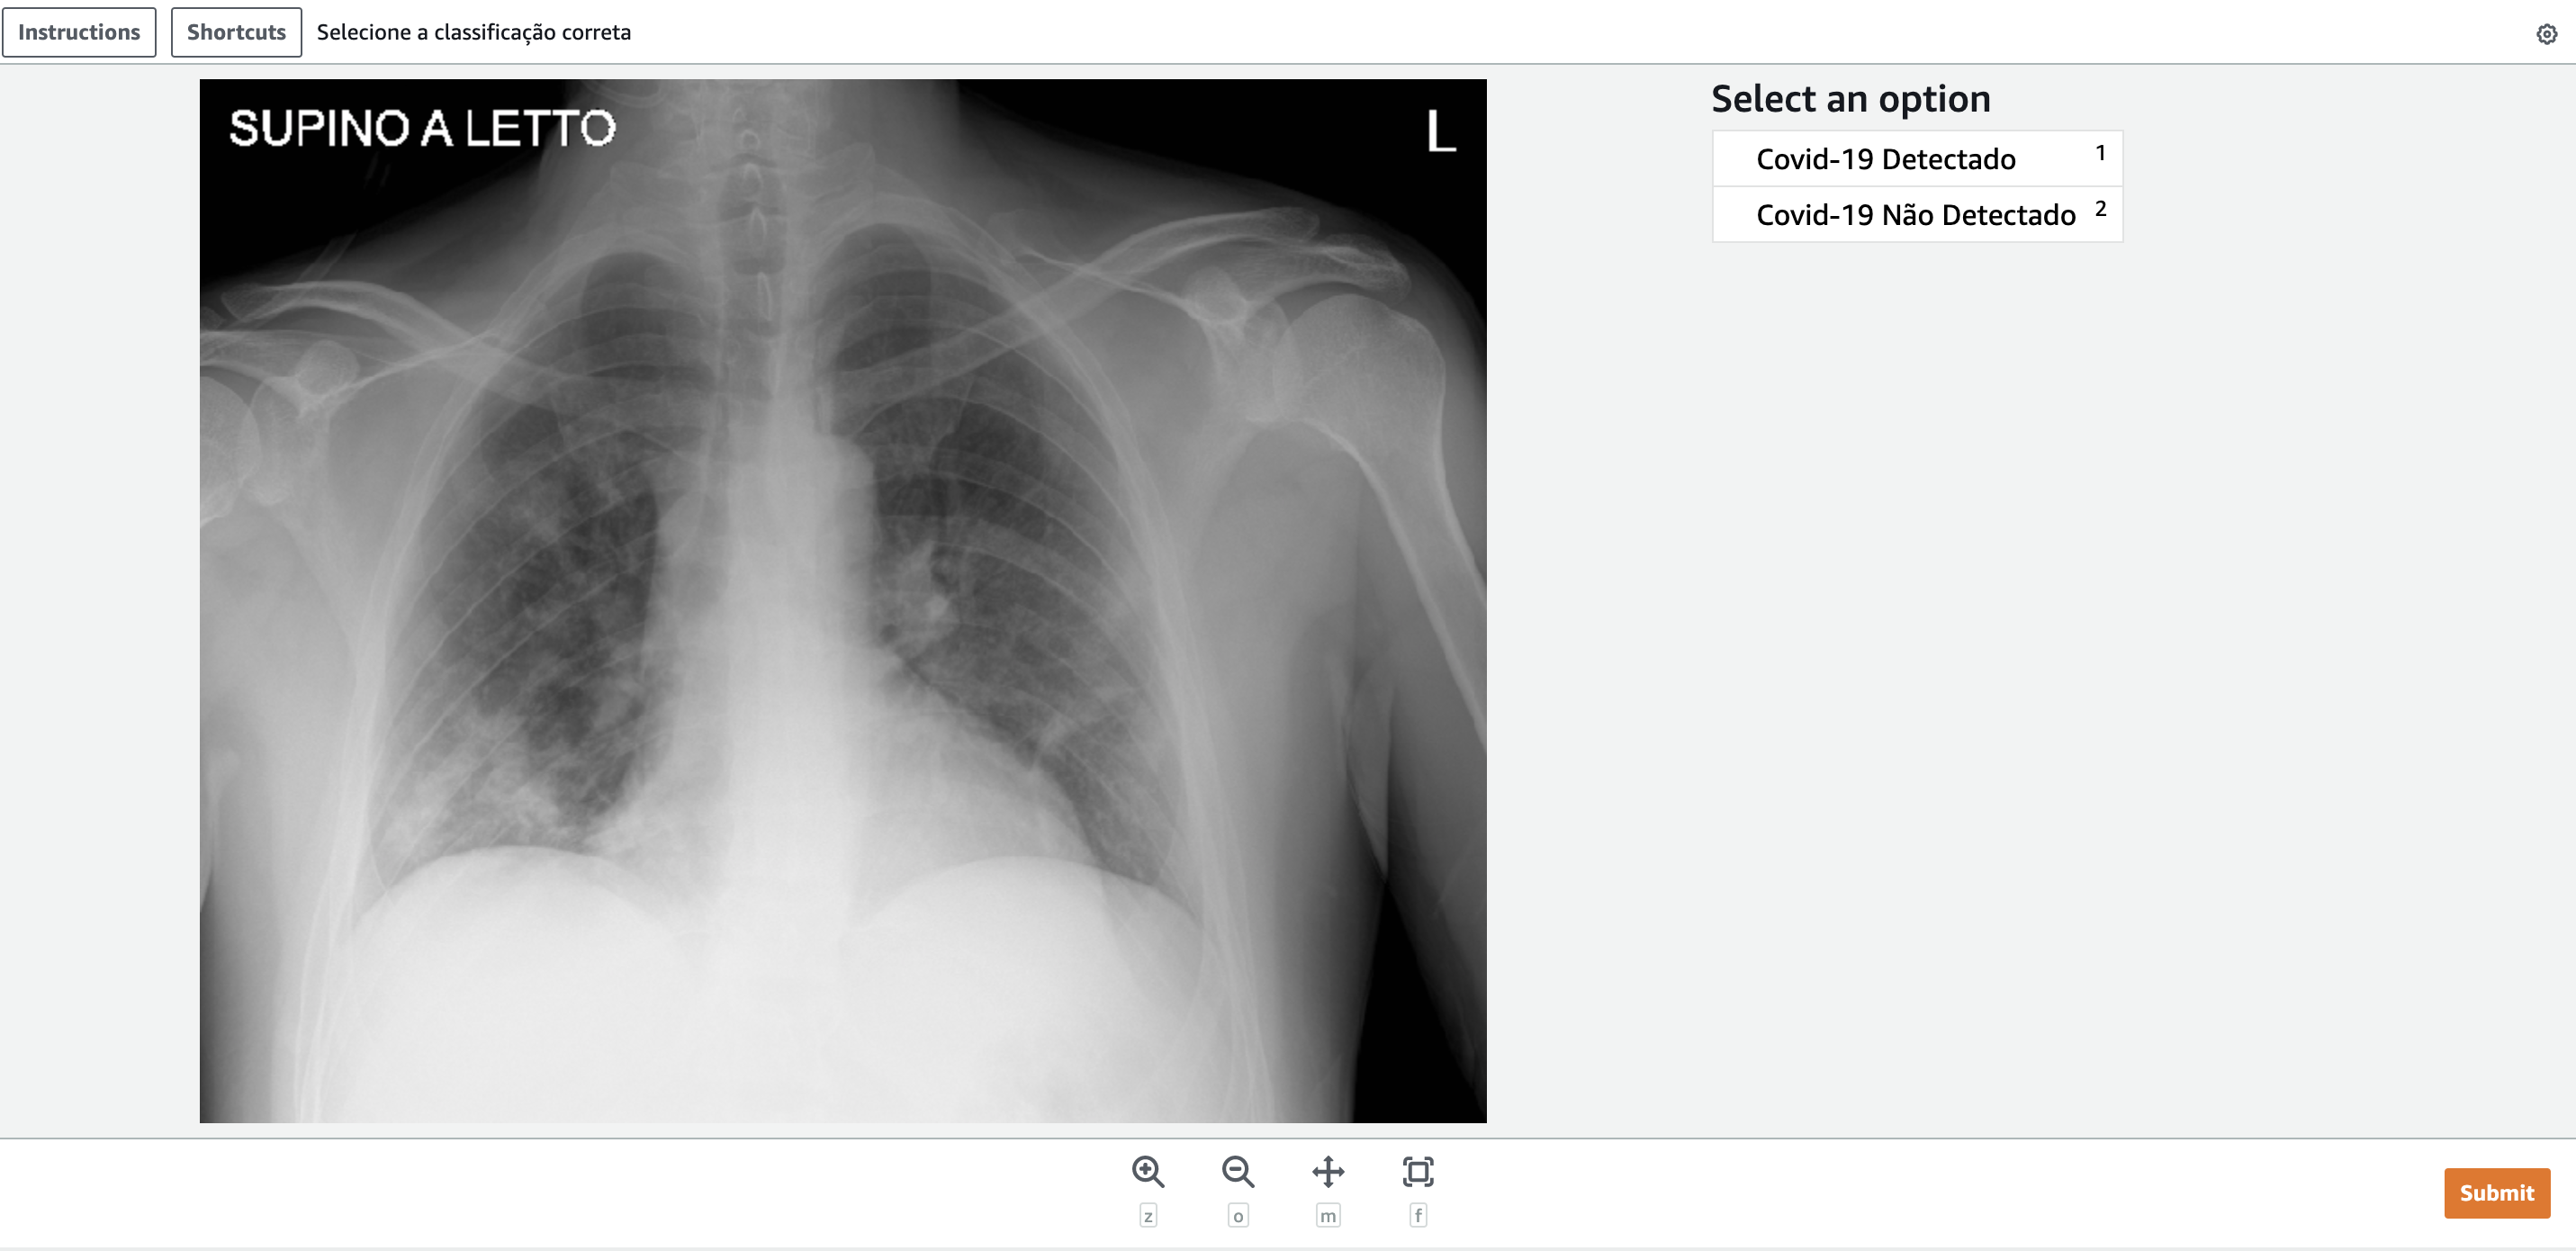

Cuando seleccionamos la tarea y hacemos clic en Comenzar a trabajar, tendremos la siguiente pantalla:

En el caso anterior, la imagen pertenecía a la clase «Detectado». Seleccionamos la opción correcta (1) y hacemos clic en «Enviar». La tarea se completará y el resultado se almacenará desde el s3 introducido en el momento de la creación del flujo.

Interesante observar que la pantalla fue creada a base de nuestra plantilla y es ampliamente personalizable para contener otras categorías, textos, descripciones y similares. En el enlace mencionado anteriormente tenemos otras sugerencias de plantillas para crear la interfaz de nuestra tarea.